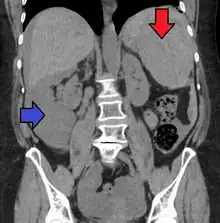

Splenic hematoma resulting in free abdominal blood

Splenic rupture is usually evaluated by FAST ultrasound of the abdomen.[5] Generally this is not specific to splenic injury; however, it is useful to determine the presence of free floating blood in the peritoneum.[5] A diagnostic peritoneal lavage, while not ideal, may be used to evaluate the presence of internal bleeding a person who is hemodynamically unstable.[6] The FAST exam typically serves to evaluate the need to perform a CT scan.[6] Computed tomography with IV contrast is the preferred imaging study as it can provide high quality images of the full peritoneal cavity.[5]